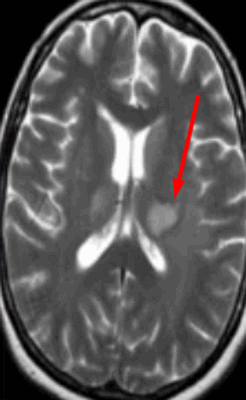

![Абсцесс головного мозга на МРТ]()

Абсцесс головного мозга на МРТ (указан стрелкой)